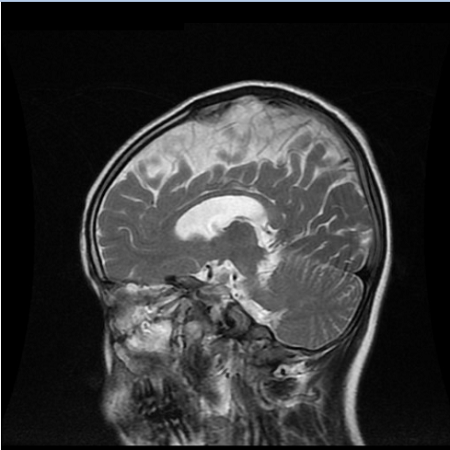

AGS临床表现非常的多样,个体间的差异也较大。多数患儿在3岁前就发病了,最常见的症状为颅内钙化、脑白质病变、脑萎缩,可伴有肌张力增高(就是肌肉紧张度增高)、运动发育落后、语言发育落后、小头畸形,伴或不伴智力发育落后等。其中颅内钙化在头颅CT上显示较清楚,多为双侧,主要分布于基底节区(图1)。脑白质病变在头颅MRI上显示较清楚,可累及脑室周围、皮质下白质、额叶和颞区等部位(图2)。脑萎缩主要显示为脑室周围区域和脑沟的扩大(图3)。也有患儿以反复发生冻疮样皮疹为突出表现,多发生在四肢末端、耳朵、面部和肘部等部位(图4),这些孩子的皮疹在冬天加重,气温变暖后可好转。如孩子出现上述症状,需及时到医院就诊。其他的临床表现还包括发热、癫痫、白细胞减少、贫血、血小板减低、转氨酶升高、肝脾肿大、肺部间质病变、甲状腺功能减退或者亚临床甲状腺功能减退、胃食管反流、关节肿胀或疼痛。轻度肺间质病变可以仅表现为肺部影像学的异常,严重者可以出现咳嗽、呼吸困难等症状。如果孩子出现了上述表现,家长切莫大意,要及时带孩子到正规医院就诊哦!

图3